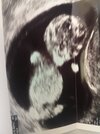

Hej ciocie, w tym czasie kiedy mama wykańcza się przy randkowaniu z muszlą to ja sobie tak pięknie rosnę, i zaczynam 11 tydzień z 4.09 cm od główki do pupy😍 powiem wam dziewczyny ze widok tego bijacego serduszka wynagradza ten ciężki czas id 2 tygodni ledwo żyję dlatego też mnie mało tutaj ale najważniejsze ze ten cukiereczek sie rozwija 😍

Załączniki

• 16950378286516158053805479805330.jpg

16950378286516158053805479805330.jpg

1,3 MB · Wyświetleń: 89